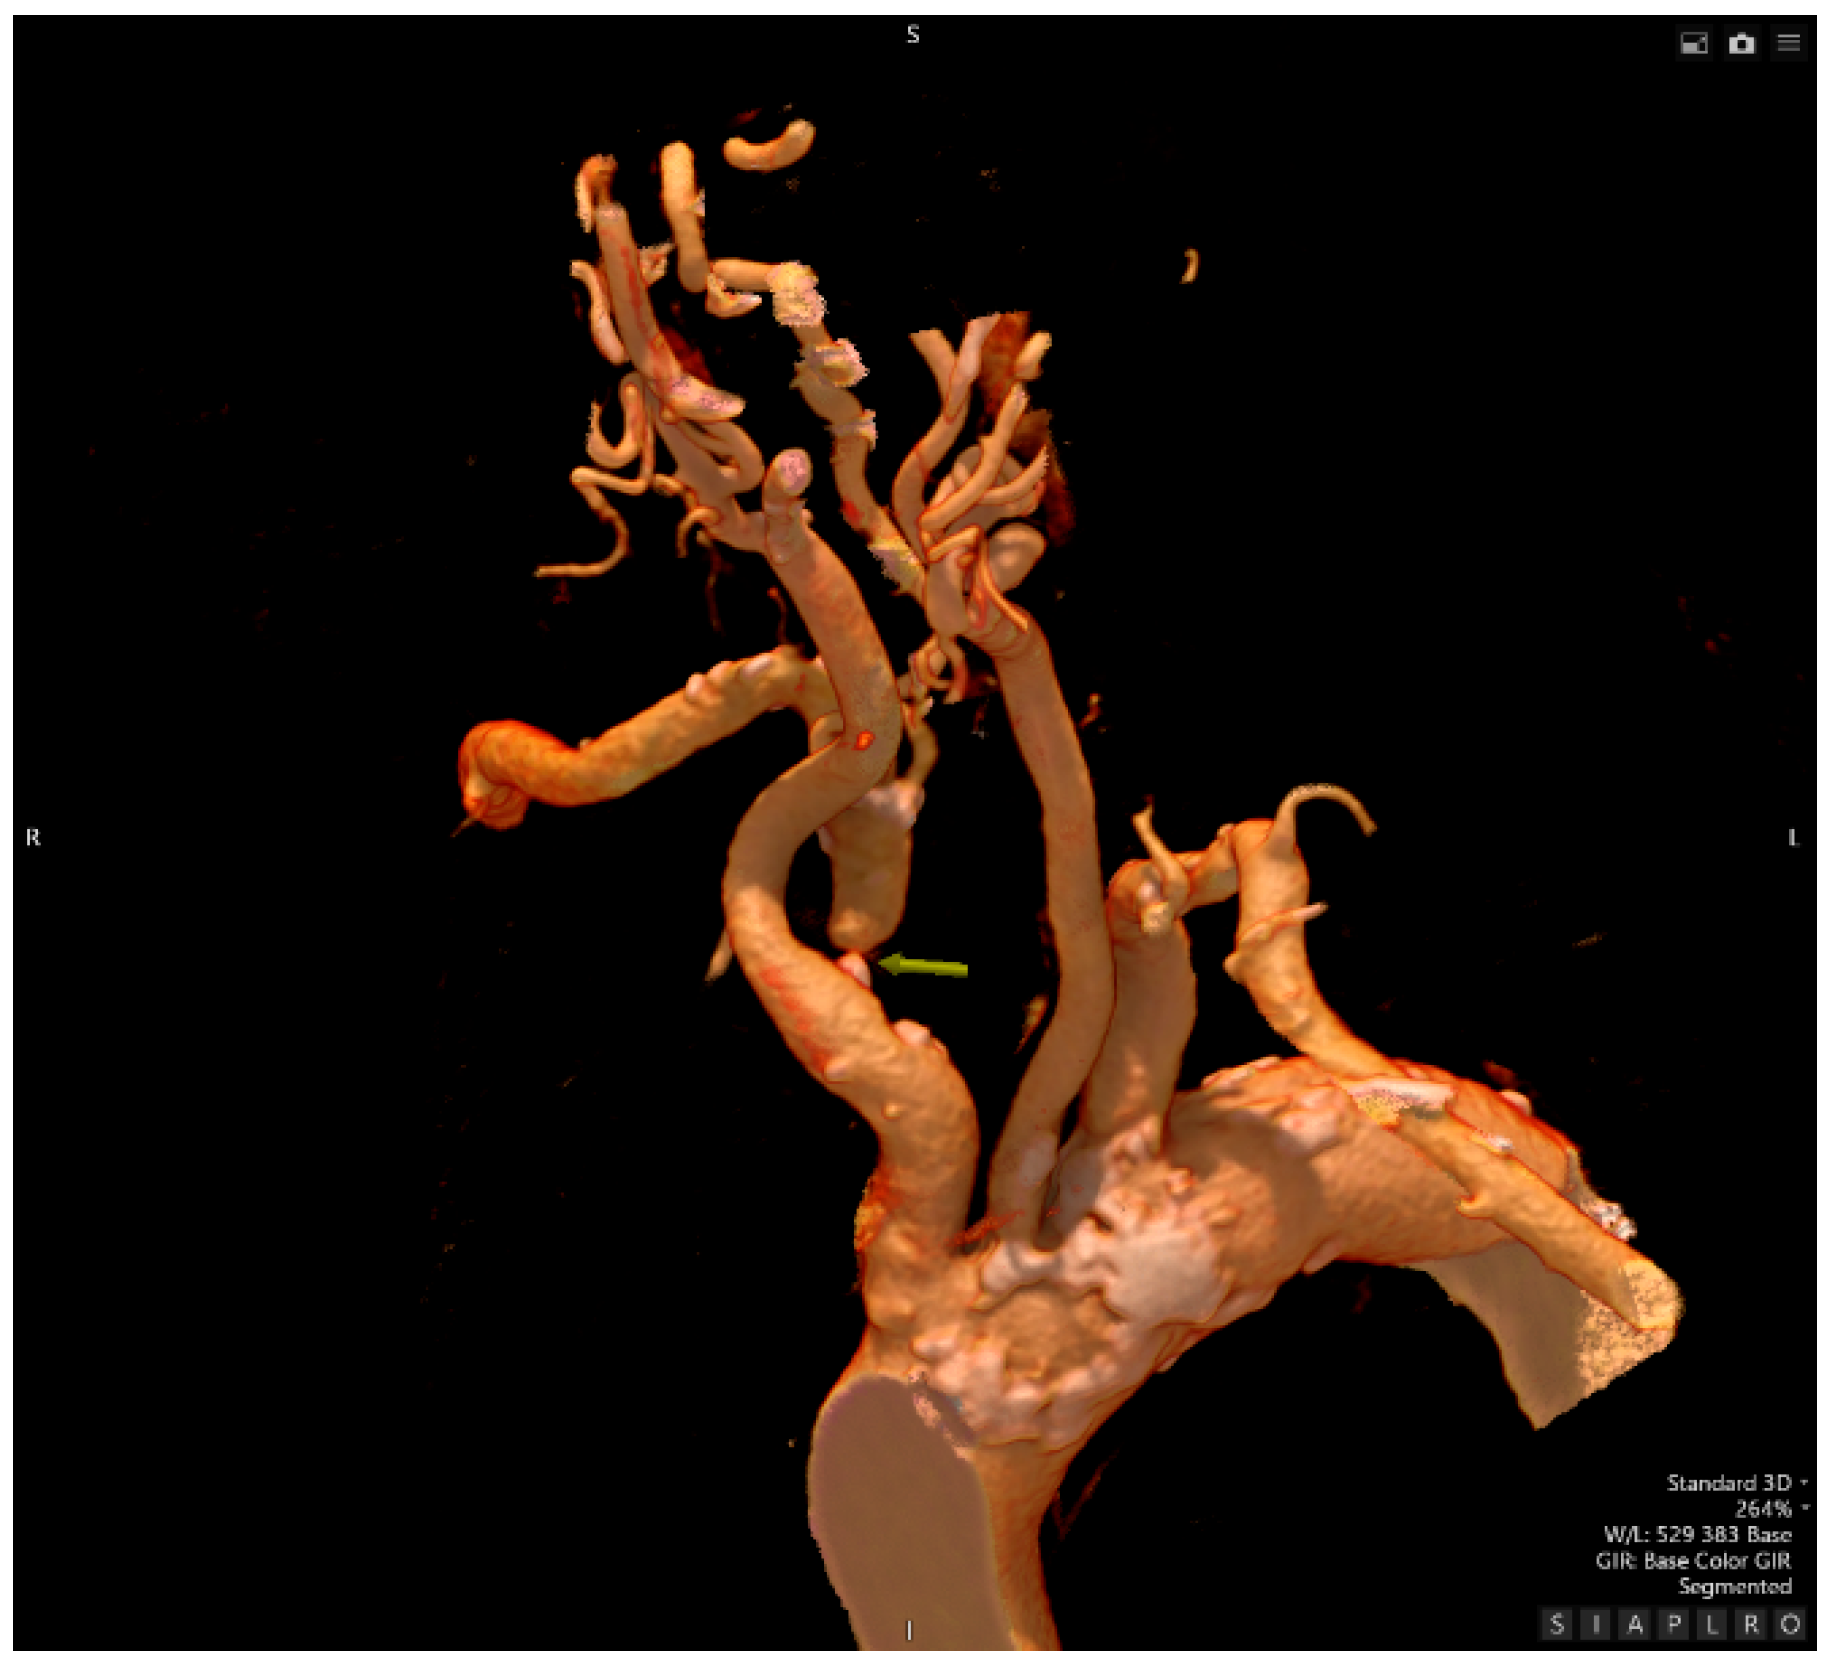

- Computed Tomography Angiography

- Interventional Radiology – an attempt at recanalization of the right subclavian artery